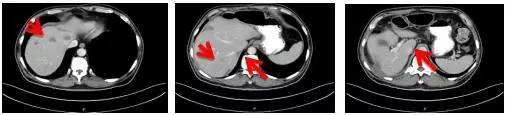

消融后继续原方案治疗6周期,随后以靶向药物贝伐珠单抗维持治疗10个周期。 2016年12月检查发现,患者体内肿瘤进展,需要调整治疗方案。经基因检测,发现KRAS、NRAS及BRAF基因V600E均未突变。遂予化疗伊立替康和靶向治疗药物爱必妥联合治疗,4周期后进入维持治疗。目前,病人一般情况好,肿瘤控制理想。

消融术后继续靶向治疗联合化疗,病情稳定未有发展

2016.7.15

2016.9.24